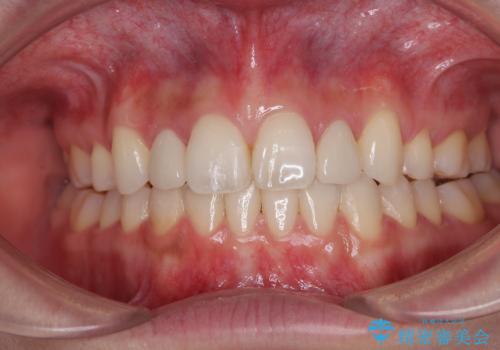

しかしながら、左右ともに側切歯が矮小歯であるため、矯正治療で矮小歯前後にスペースを作り、矯正治療後にオールセラミッククラウンにて補綴治療を行うこととしました。

治療途中で地元へ転居され、飛行機での通院となったため、治療期間が長くなりましたが、自然で整った口元に仕上げることができました。